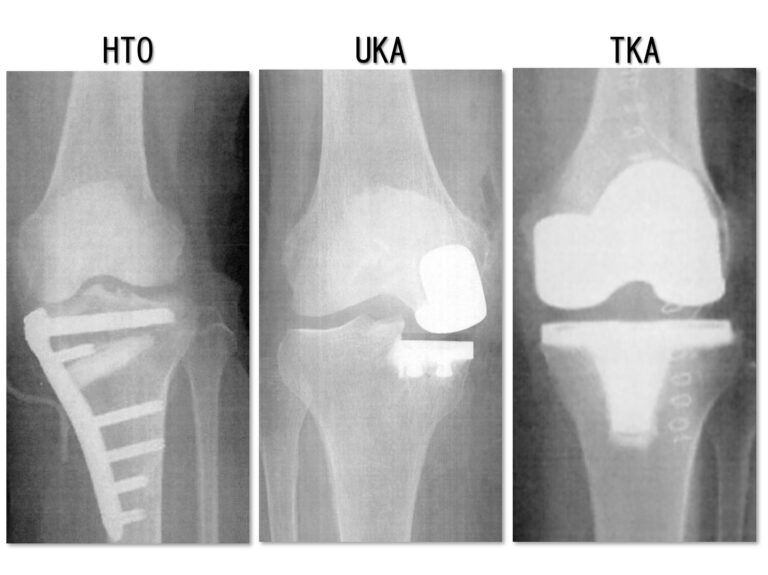

③HTO・DTO

④UKA

⑤TKA

| HTO | UKA | TKA | |

|---|---|---|---|

| 年齢 | 40歳から70歳くらいまで | 70歳後半〜 | 60歳以上 |

| 患者像 | 中高年のスポーツ愛好家 | 80歳くらいの女性 やせ型〜中背 | 70歳〜80歳のO脚 肥満でも可 |

| 痛みの部位 | 内側 | 内側 | 内側、外側 |

| 入院期間 | 3ー4週 | 2ー3週 | 3週 |

| 重度のO脚 アライメント矯正は | 改善する可能性がある | 改善しない | 改善する可能性がある |

| 術前可動域 | 拘縮は不可 | 拘縮は不可 | 拘縮でも可 |

| 出血 | △ | 〇 | × |

| 自分の骨の温存 | 〇 | △ | × |

| インプラント | 1年で抜釘 将来的にTKA可 | 温存 ゆるめば再TKA | 温存 ゆるめば再TKA |

| 50歳〜70歳 | ◎ | △ | △〜〇 |

| 80歳以上 | △ | 〇 | 〇 |

| 重労働やスポーツ | ◎ | △ | △ |

| 重度のO脚 | △〜〇 | × | 〇 |

| 外側も悪い | × | × | 〇 |

| 可動域悪い | × | △〜× | 〇 |

| 肥満 | △〜× | △〜× | △〜〇 |

| MRIで前十字靭帯断裂 | × | × | 〇 |

| 糖尿病 | △〜〇 | △〜× | △〜× |